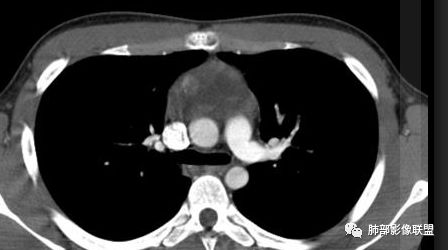

水晶石头:患者老年男性,发现皮肤粘膜黄染5天,右肺占位1天。

胸部CT:右肺中叶内侧段紧邻心脏实性结节,边缘光滑,边界清楚,宽基底与胸膜相连,内可见不规则钙化,钙化内见点状低密度影,增强中度强化,综合考虑良性病变。畸胎瘤可能大,鉴别胸膜孤立性纤维瘤及胸腺瘤。

王秀仙:右侧前纵隔肿块,边缘分叶,周围肺组织推移,宽基底与纵隔胸膜相连,可见胸膜尾征,密度不均,病灶中心可见斑块状钙化,右侧内乳动脉位于病灶前外侧并略增粗,实性成分明显强化,考虑纵隔畸胎瘤,鉴别胸腺瘤。

蓝天白云:定位纵隔,病灶呈实性成分,内见钙化,钙化位于病灶中心,实性成分均匀延迟强化,考虑良性病变,如果胸膜起源考虑sft,纵隔来源胸腺瘤,鉴别畸胎瘤。黄勇老师说过右侧心膈角区可以发生胸腺瘤

右侧前纵膈肿块,边缘分叶,病灶中心可见斑块状钙化,实性成分明显持续强化,考虑胸腺瘤。